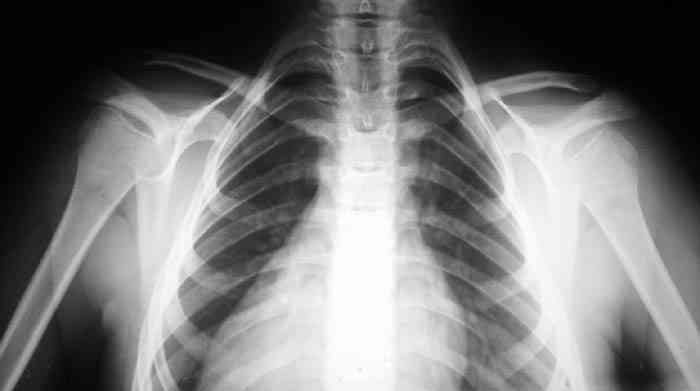

Девочка, 9 лет. Жалобы на деформацию верхнего плечевого пояса.

Объективно: приведение обоих надплечий, объем движений в плечевых суставах в полном объеме, общесоматический статус без патологии, УЗИлопаточных областей - без патологии.

Возможно речь идёт о добавочных шейных рёбрах, для уточнения целесообразно сделать боковую рентгенографию.

Наличие ключиц на прямом снимке, снимает диагноз врожденного отсутствия ключиц.

Предлагаю пока рабочим диагнозом считать: "Врожденная аномалия грудной клетки. Добавочные шейные ребра".